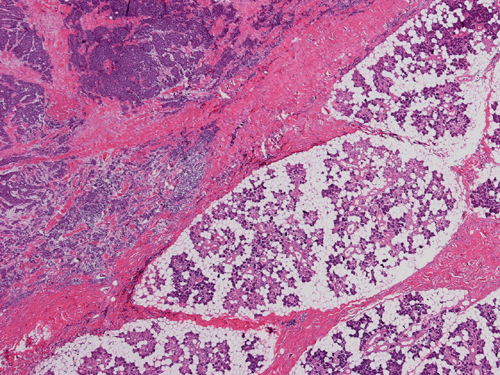

The mass appears to be a subcutaneous tumor that spares the dermis and epidermis (Panel A). On scanning magnification, the tumor has a infiltrative growth pattern (Panel B). Intrestingly, the tumor does not really invade into the parotid gland (Panel C). On medium magnification, the tumor cells arrange in irregular islands with a solid pattern (Panel D). On high magnification, the tumor cells have medium sized large nuclei with high nuclear to cytoplasmic ratio (Panel E) and scant amount of cytoplasm. The cytoplasmic membrane is not distinct. The nuclei have a coarse salt and pepper like pattern and without prominent nucleoli. On immunohistochemistry, strongly positive expression of CK20 in terms of dots are present in many of the tumor cells (Panel F). A similar but stronger staining pattern with antibodies against neurofilament proteins (Panel G).  The tumor cells are also positive for synaptophysin (Panel H).

Merkel cell carcinoma (MCC) is an uncommon, highly malignant cutaneous tumor with a mortality of 33 % which is the highest of any cutaneous malignancy. It predominantly involves the head and neck area and arises in the dermis.  The salient features include a small blue cell tumor type of histology with neuroendocrine immumohistochemical profile, arising in the dermis, a high rate of local recurrence, aggressive regional nodal invasion, and distant metastases.

Macroscopically, MCCs are typicalaly 2 to 4 cm firm, non-tender, dome-shaped red, violaceous or purple nodule located on sun exposed regions of the body.  The overlying skin is usually smooth, shiny and can exhibit ulcerative, acneiform or telangiectatic features. In greater than 50 % of cases it will involve the head and neck, the extremities in 40 % and the trunk in less than 10 %. The rapidity of growth may be the only feature suggesting malignancy. It often behaves like a melanoma, with an orderly progression of lymph node involvement, allowing lymphoscintigraphy to be utilized in localizing sentinel lymph nodes.